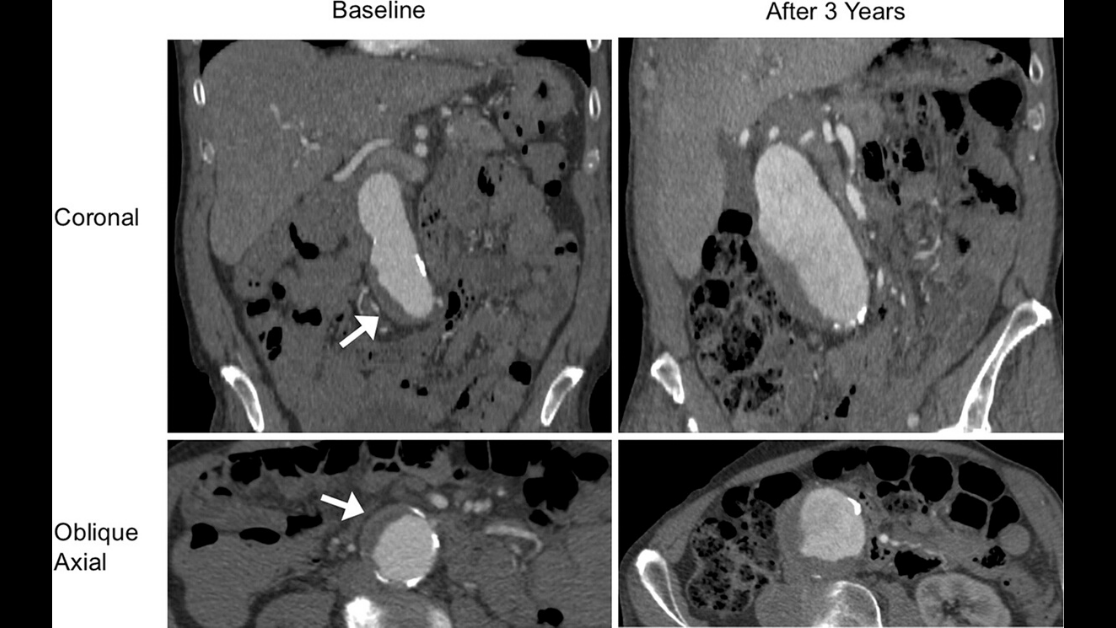

Thermal ablation and nephrectomy yielded comparable 5-year survival in patients over age 65 years with Stage 1A renal cell carcinoma. http://ow.ly/mb1830kMEYg pic.twitter.com/ObrhaPYvem